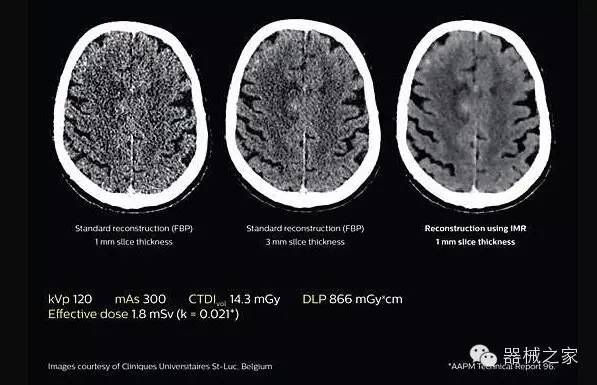

2.腦部顯影

透過數(shù)字化影真芯片DAS系統(tǒng)、球面微平板探測(cè)器技術(shù)和濾線柵技術(shù)等硬件技術(shù),整體提高探測(cè)器成像的能力,奠定低劑量條件下高清成像的基礎(chǔ);

應(yīng)用目前業(yè)界領(lǐng)先的新一代星光平臺(tái)iDose4 Premium及基于迭代基礎(chǔ)的O一MAR去除金屬偽影技術(shù),達(dá)成微量輻射下零偽影的高清晰成像;